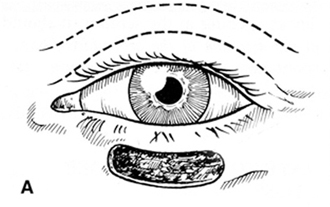

Con tijeras de Wescott, procedemos a incidir las fibras longitudinales del músculo orbicular, en sentido longitudinal , tanto en la línea del pliegue palpebral como en la línea de incisión superior, liberando así totalmente el colgado mío-cutáneo , que queda unido a su lecho original solamente por los pedículos laterales. (Figura 4)

Figura 4 Colgajo Bipediculado